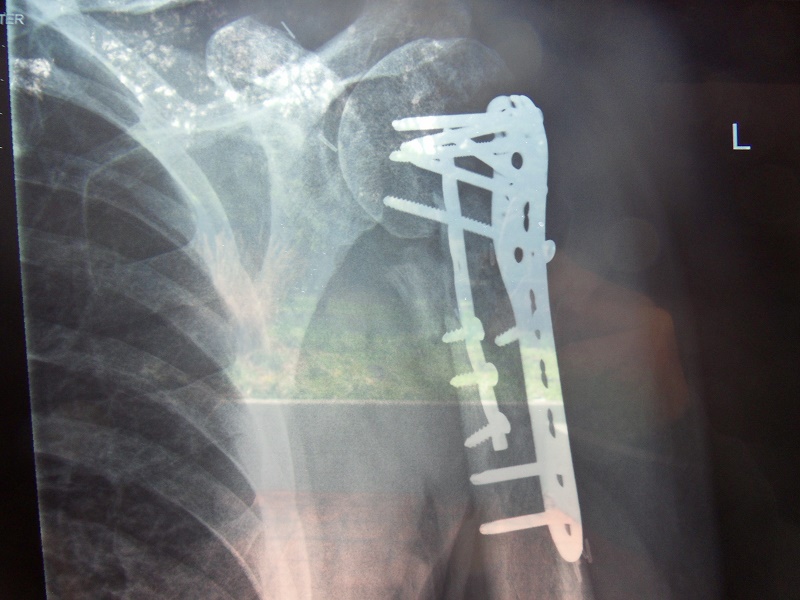

The pictures pretty well sum up the story...